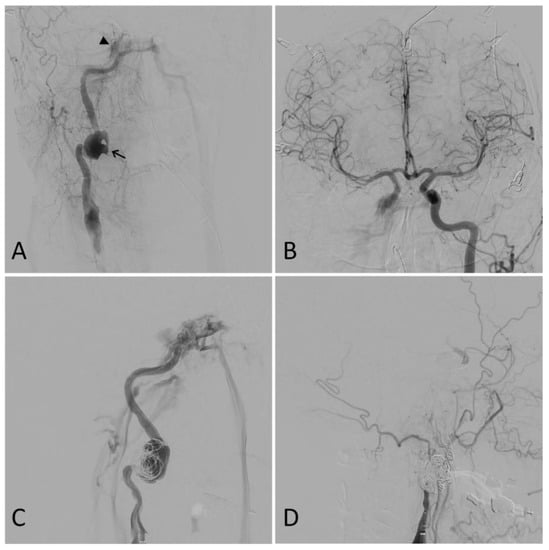

3.2. Grade III: Pseudoaneurysm